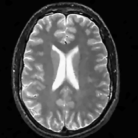

The comparison of the methods in the context of random sampling with 20% of the samples retained in the absence of noise is shown in Fig. 4. The regularization parameters of all the algorithms have been optimized to yield the best signal to noise ratio (SNR). The SNR and the peak SNR (PSNR) that are used for the comparisons in this paper are computed as

We observe that the proposed non-local algorithm provides better preservation of edge details and minimize patchy artifacts as seen in TV reconstructions. The quantitative comparisons of different methods on more MR images in the absence of noise using 5 fold random sampling operator are reported in Table III. We observe that the NLS scheme provides a consistent 2-4 dB improvement over the other methods in most cases.

Refer to caption

(a) Original

(b) DLMRI, SNR=20.46

(c) TV, SNR=22.80

(d) NLS, SNR=28.41

(e) Sampling pattern

(f) DLMRI error

(g) TV error

(h) NLS error

Figure 4: Comparison of the algorithms in the absence of noise. We consider the recovery of a 256×\times256 MRI brain image from 20% of its Fourier samples, acquired using a random sampling pattern shown in (e) using non-local shrinkage scheme (NLS), DLMRI and local TV (TV). The reconstructions are shown in (b)-(d). The corresponding error images, scaled by a factor of 5 for better visualization, are shown in the bottom row. The reconstructions show that the NLS scheme is capable of better preserving the edges and details, resulting in less blurred reconstructions.